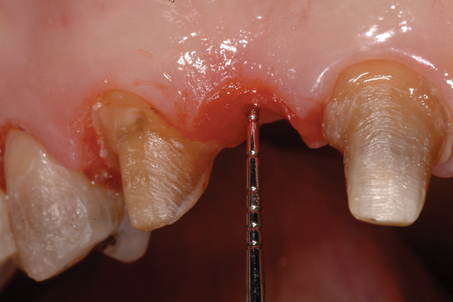

(12.) Bone sounding was performed to confirm that there was at least 2 mm from the base of the pontic sites to the alveolar bone.

Figure 12

The distance between the bottom of the ovate pontic site and the alveolar bone is determined using a periodontal probe to sound for the bone. If the measured distance is 2 mm or greater (Figure 4), then there is adequate tissue thickness to meet the prosthetic biologic width requirements, and the provisional restoration can be cemented with provisional cement. However, if the tissue thickness is less than 2 mm, then there is not adequate tissue present to meet the prosthetic biologic width requirements (Figure 5), and the pontic site must be deepened using a teardrop-shaped diamond bur (Figure 6). The remaining soft tissue and enough alveolar bone are removed to result in the required 2-mm distance from the most subgingival aspect of the pontic to the alveolar bone. It is essential that the intaglio surface of the pontic be correctly contoured before the reshaping of the pontic site. The provisional bridge can then be cemented with a provisional cement and the provisional pontic will direct the regrowth of the soft tissue.

The distance between the bottom of the ovate pontic site and the alveolar bone is determined using a periodontal probe to sound for the bone. If the measured distance is 2 mm or greater, then there is adequate tissue thickness to meet the prosthetic biologic width requirements. However, if the tissue thickness is less than 2 mm, then the pontic site must be deepened using a teardrop-shaped diamond bur until enough alveolar bone is removed to result in the required 2-mm distance. Hemostasis is accomplished with an astringent, and then the bridge can either be cemented or bonded.